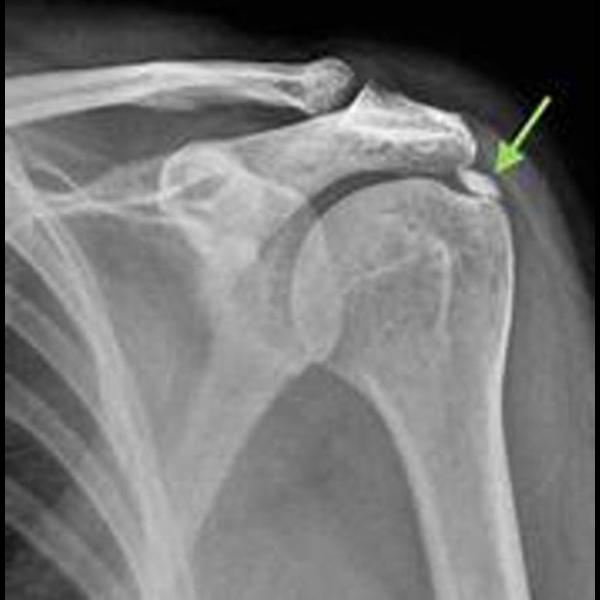

Calcification of the Supraspinatus Tendon: Cause o...